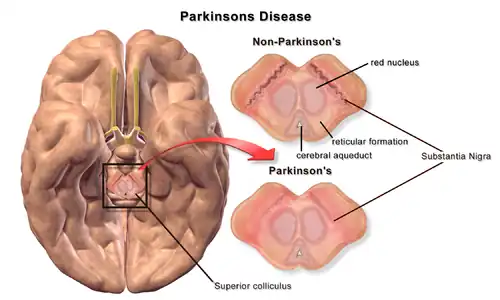

Degradation of substantia nigra associated with Parkinson's disease.

Degradation of substantia nigra associated with Parkinson's disease. -